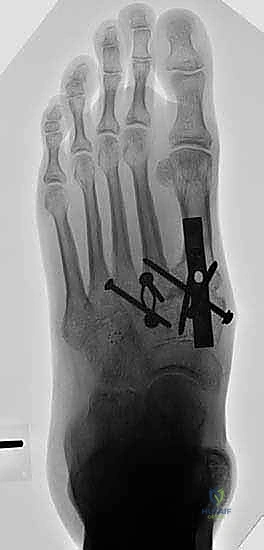

لضمان التحام العظام لتصبح عظمة واحدة صلبة، يجب تثبيتها بقوة هائلة حتى لا تتحرك أثناء فترة الشفاء. يتم استخدام مسامير معدنية متطورة (Screws)، أو شرائح معدنية خاصة (Plates)، أو دبابيس طبية متخصصة (Staples) مصنوعة من التيتانيوم الآمن على الجسم.

بعد التأكد التام من وضع العظام وثباتها باستخدام جهاز الأشعة السينية داخل غرفة العمليات (C-Arm)، يتم إغلاق الشقوق الج